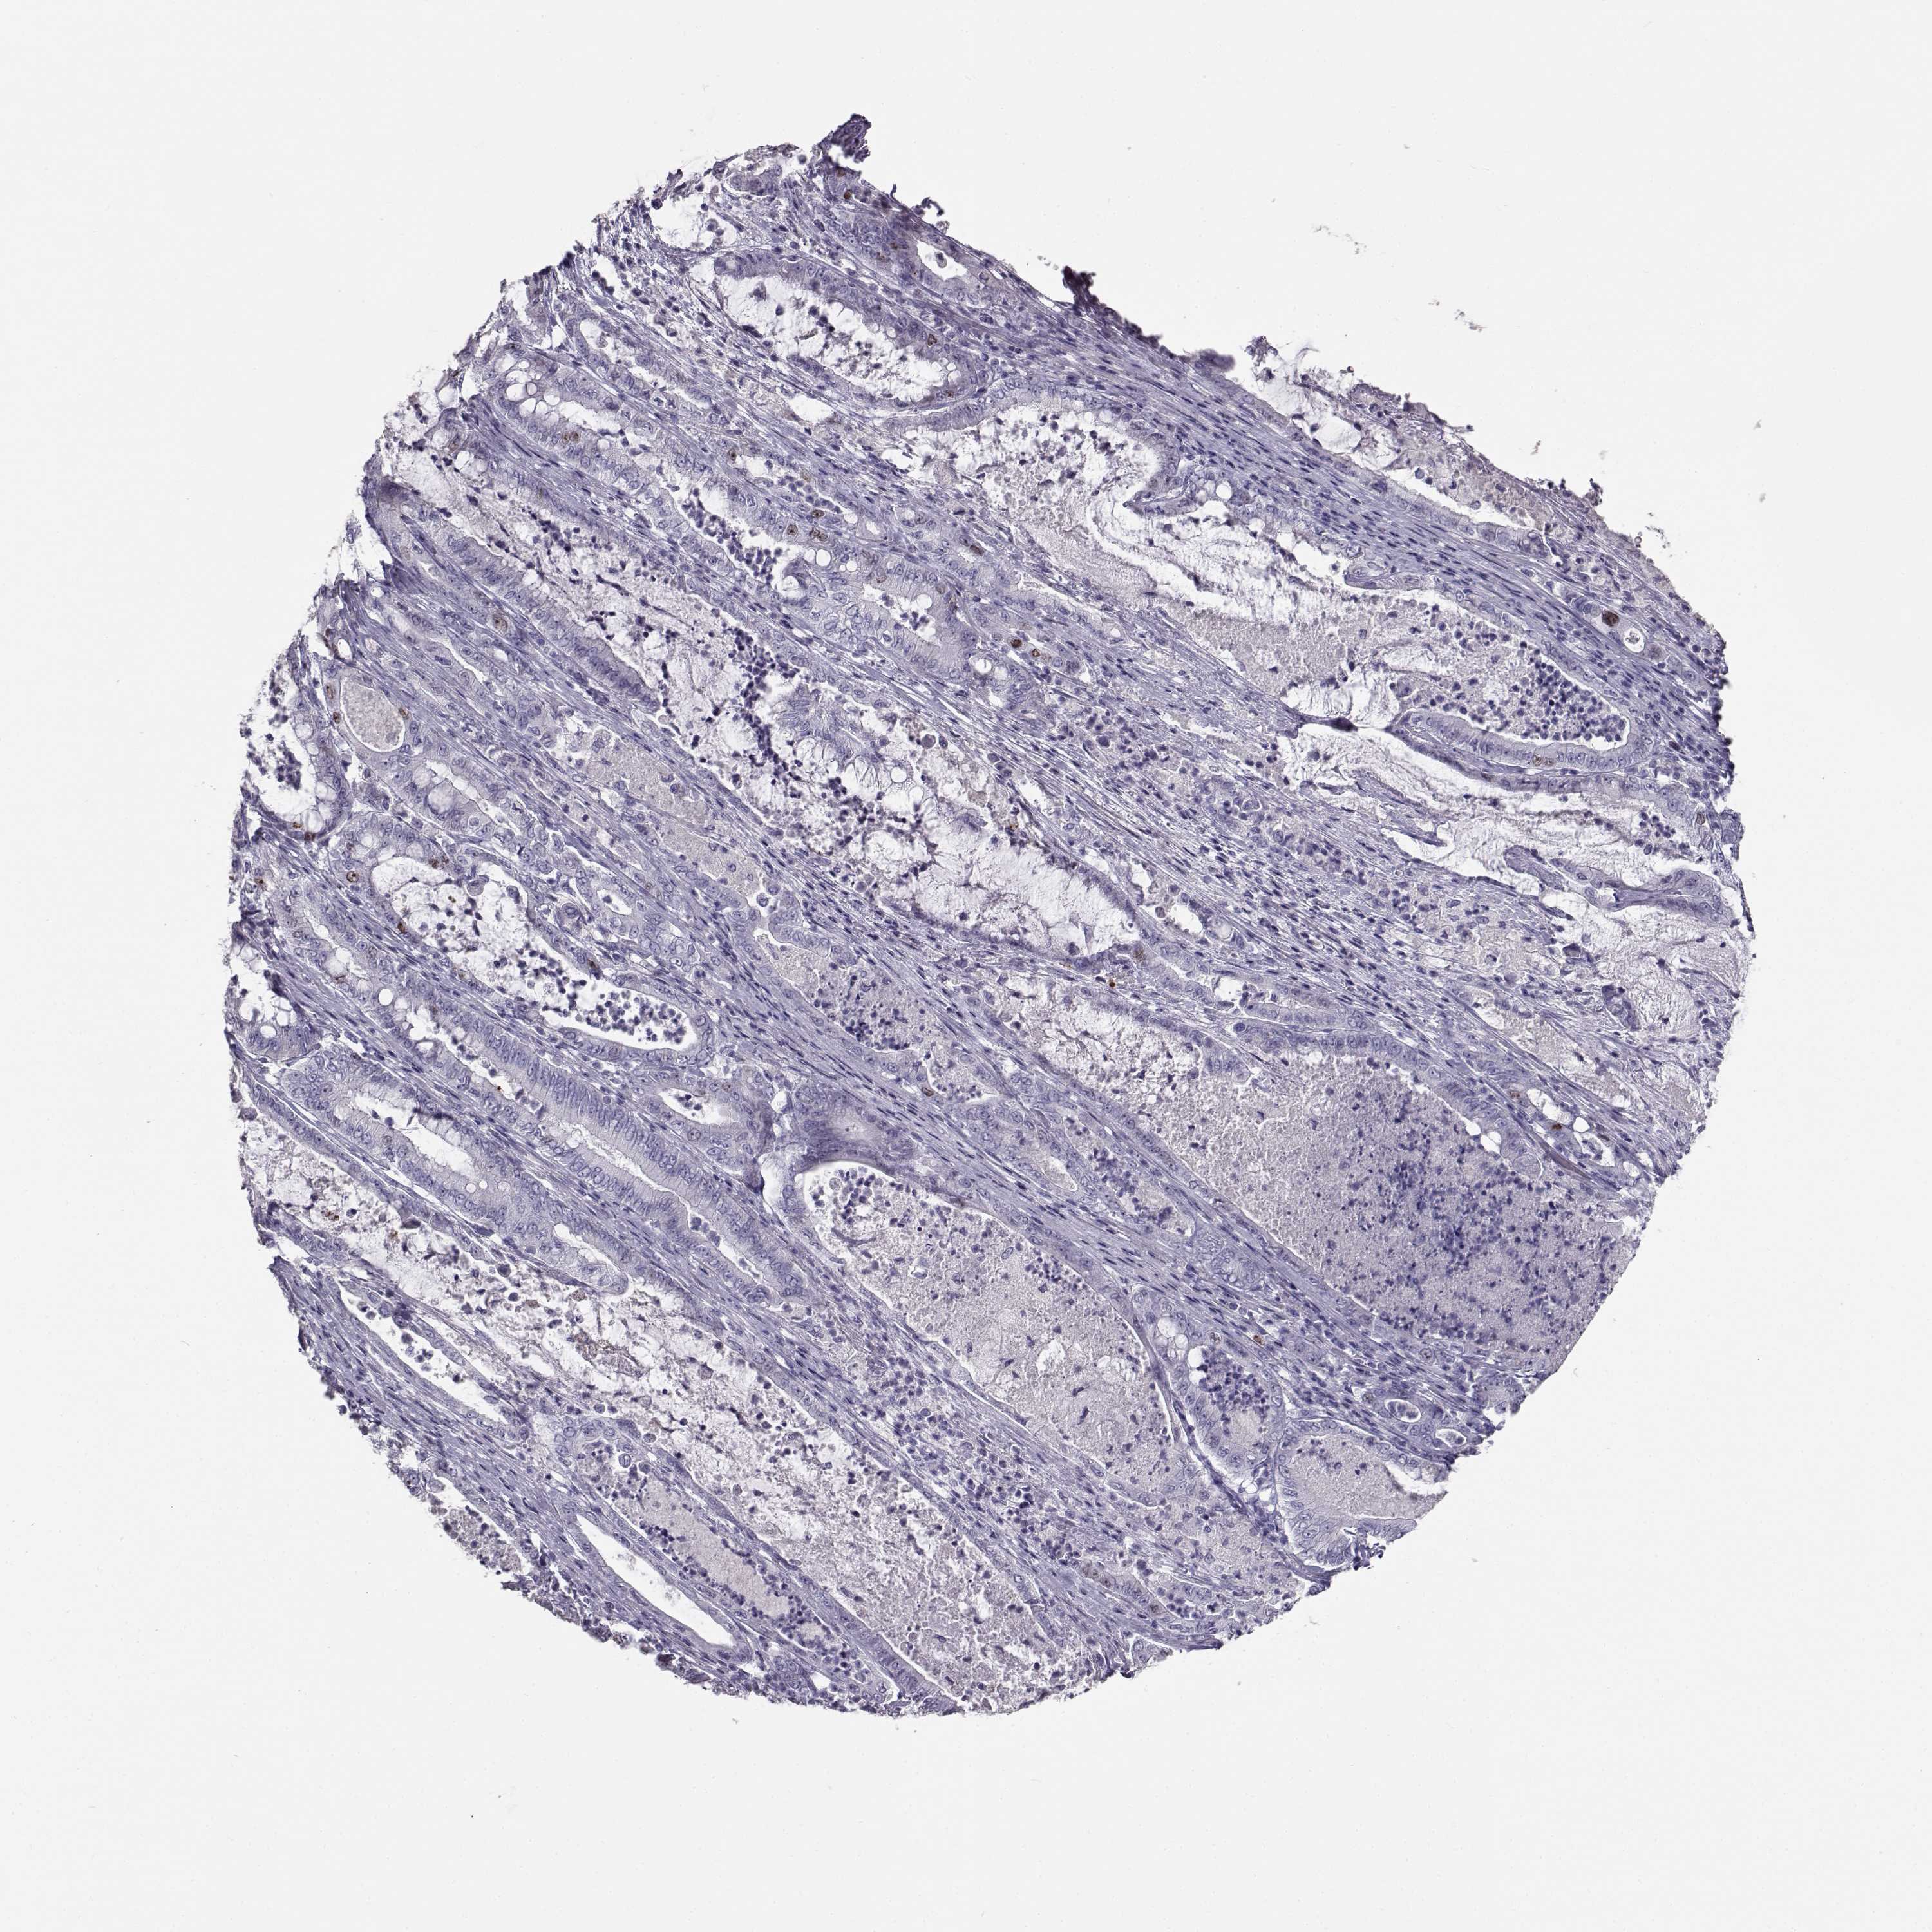

PANCREATIC CANCER - Protein expressioni

A mouse-over function shows sample information and annotation data. Click on an image to view it in a full screen mode. Samples can be filtered based on level of antibody staining by selecting one or several of the following categories: high, medium, low and not detected. The assay and annotation is described here.

Note that samples used for immunohistochemistry by the Human Protein Atlas do not correspond to samples in the TCGA dataset.

Antibody stainingi

Antibody staining in the annotated cell types in the current human tissue is reported as not detected, low, medium, or high, based on conventional immunohistochemistry profiling in selected tissues. This score is based on the combination of the staining intensity and fraction of stained cells.

Each image is clickable and will lead to virtual microscopy that enables deeper exploration of all samples and also displays staining intensity scores, fraction scores and subcellular localization as well as patient and tissue information for each sample.

Antibody HPA064874

Staining

High

Medium

Low

Not detected

Intensity

Strong

Moderate

Weak

Negative

Quantity

>75%

75%-25%

<25%

None

Location

Nuclear

Cytoplasmic/membranous

Cytoplasmic/membranous,nuclear

Adenocarcinoma, NOS